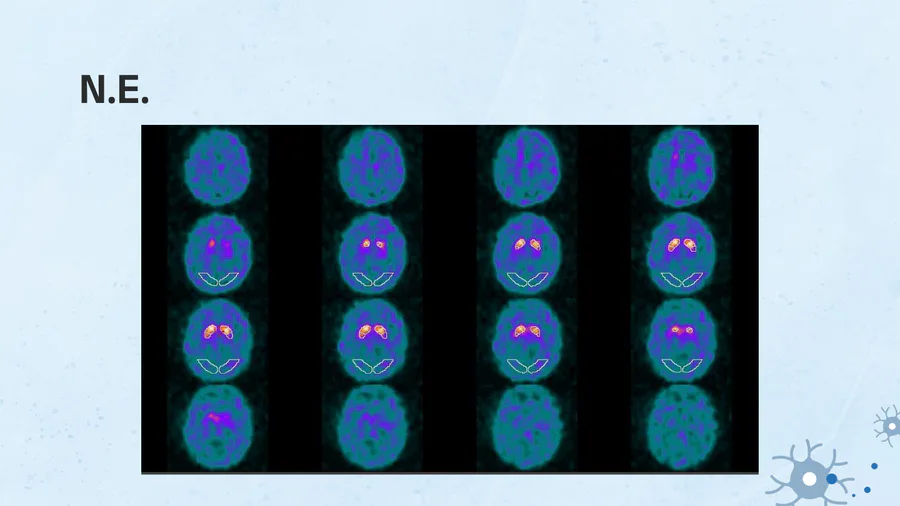

Yorumunuz nedir?

Presinaptik dopaminerjik yolakta kayıp lehine bulgular mevcuttur.

Normal sınırlarda I-123 Ioflupan çalışması